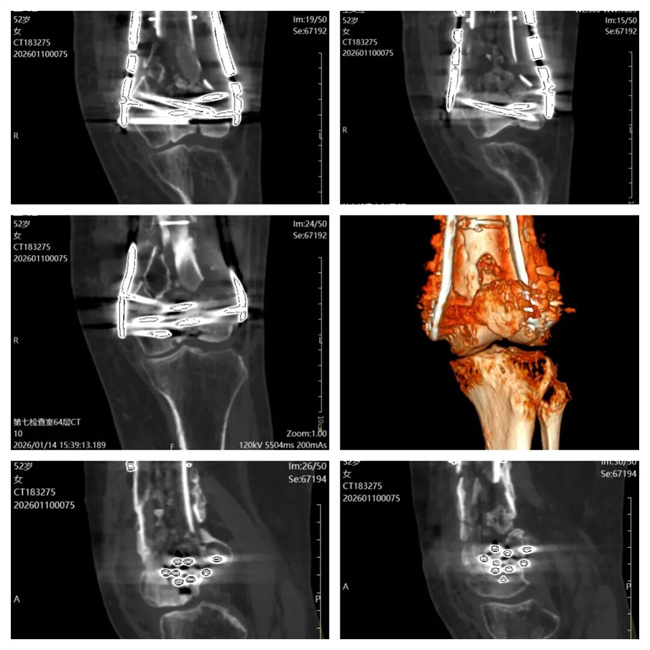

一、患者王某某,女,52岁,患者左膝部骨折术后7月,膝关节活动受限,查体左大腿内侧窦道形成,肌肉萎缩。为求进一步治疗,来到我院请专家会诊,通过各位专家会诊查体、查看影像资料并细致认真的分析后,诊断为:右股骨远端骨折术后感染,意见:住院治疗,做(窦道)造影,抗感染治疗。